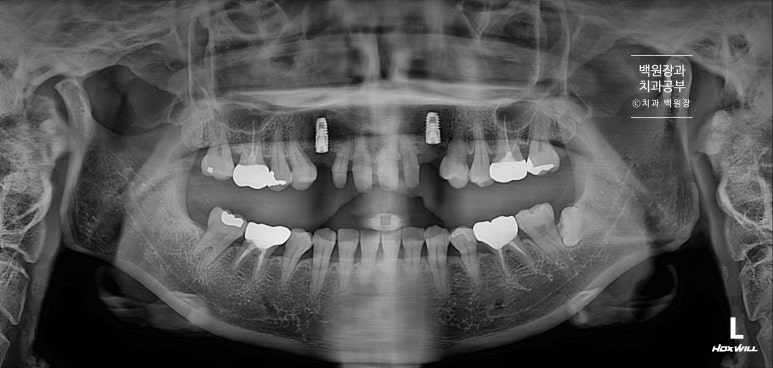

치료 완료 후 치과용 파노라마 엑스레이 사진입니다!

아주 깔끔하게 6개의 크라운이 잘 제작되어 있는 것을 보실 수 있을거에요.

치료 전 후를 비교해보면, 여섯개의 크라운이 따로 제작되어 모두 떨어져 있는 형태를 가지고 있고 두개의 임플란트는 아주 가지런한 방향으로 잘 수술되어 있는 것을 보실 수 있을겁니다.